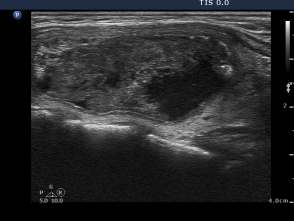

Three month prior to sclerotherapy (1st row of images)

Clinical presentation: a 50-year-old woman noticed a lump in the neck for 3 months. Thesize of the lesion did not changed over time.

Palpation: a firm nodule in the left lobe. The lesion was painless.

Functional state: euthyroidism with TSH 1.08 mIU/L.

Ultrasonography: the thyroids were echonormal. A large central-type cyst occupied almost the entire left lobe.

We tried to remove the cystic fluid but only 1.5 ml brown gelatinous fluid could be aspirated. Aspiration cytology resulted in benign cystic lesion.

We suggested a repeat aspiration 3 months later.